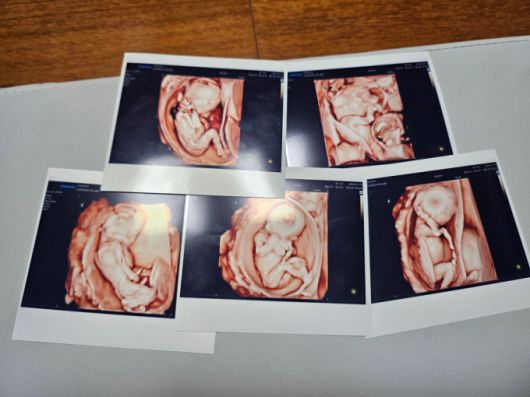

[사진=서울성모병원] 오둥이 태아 사진 |